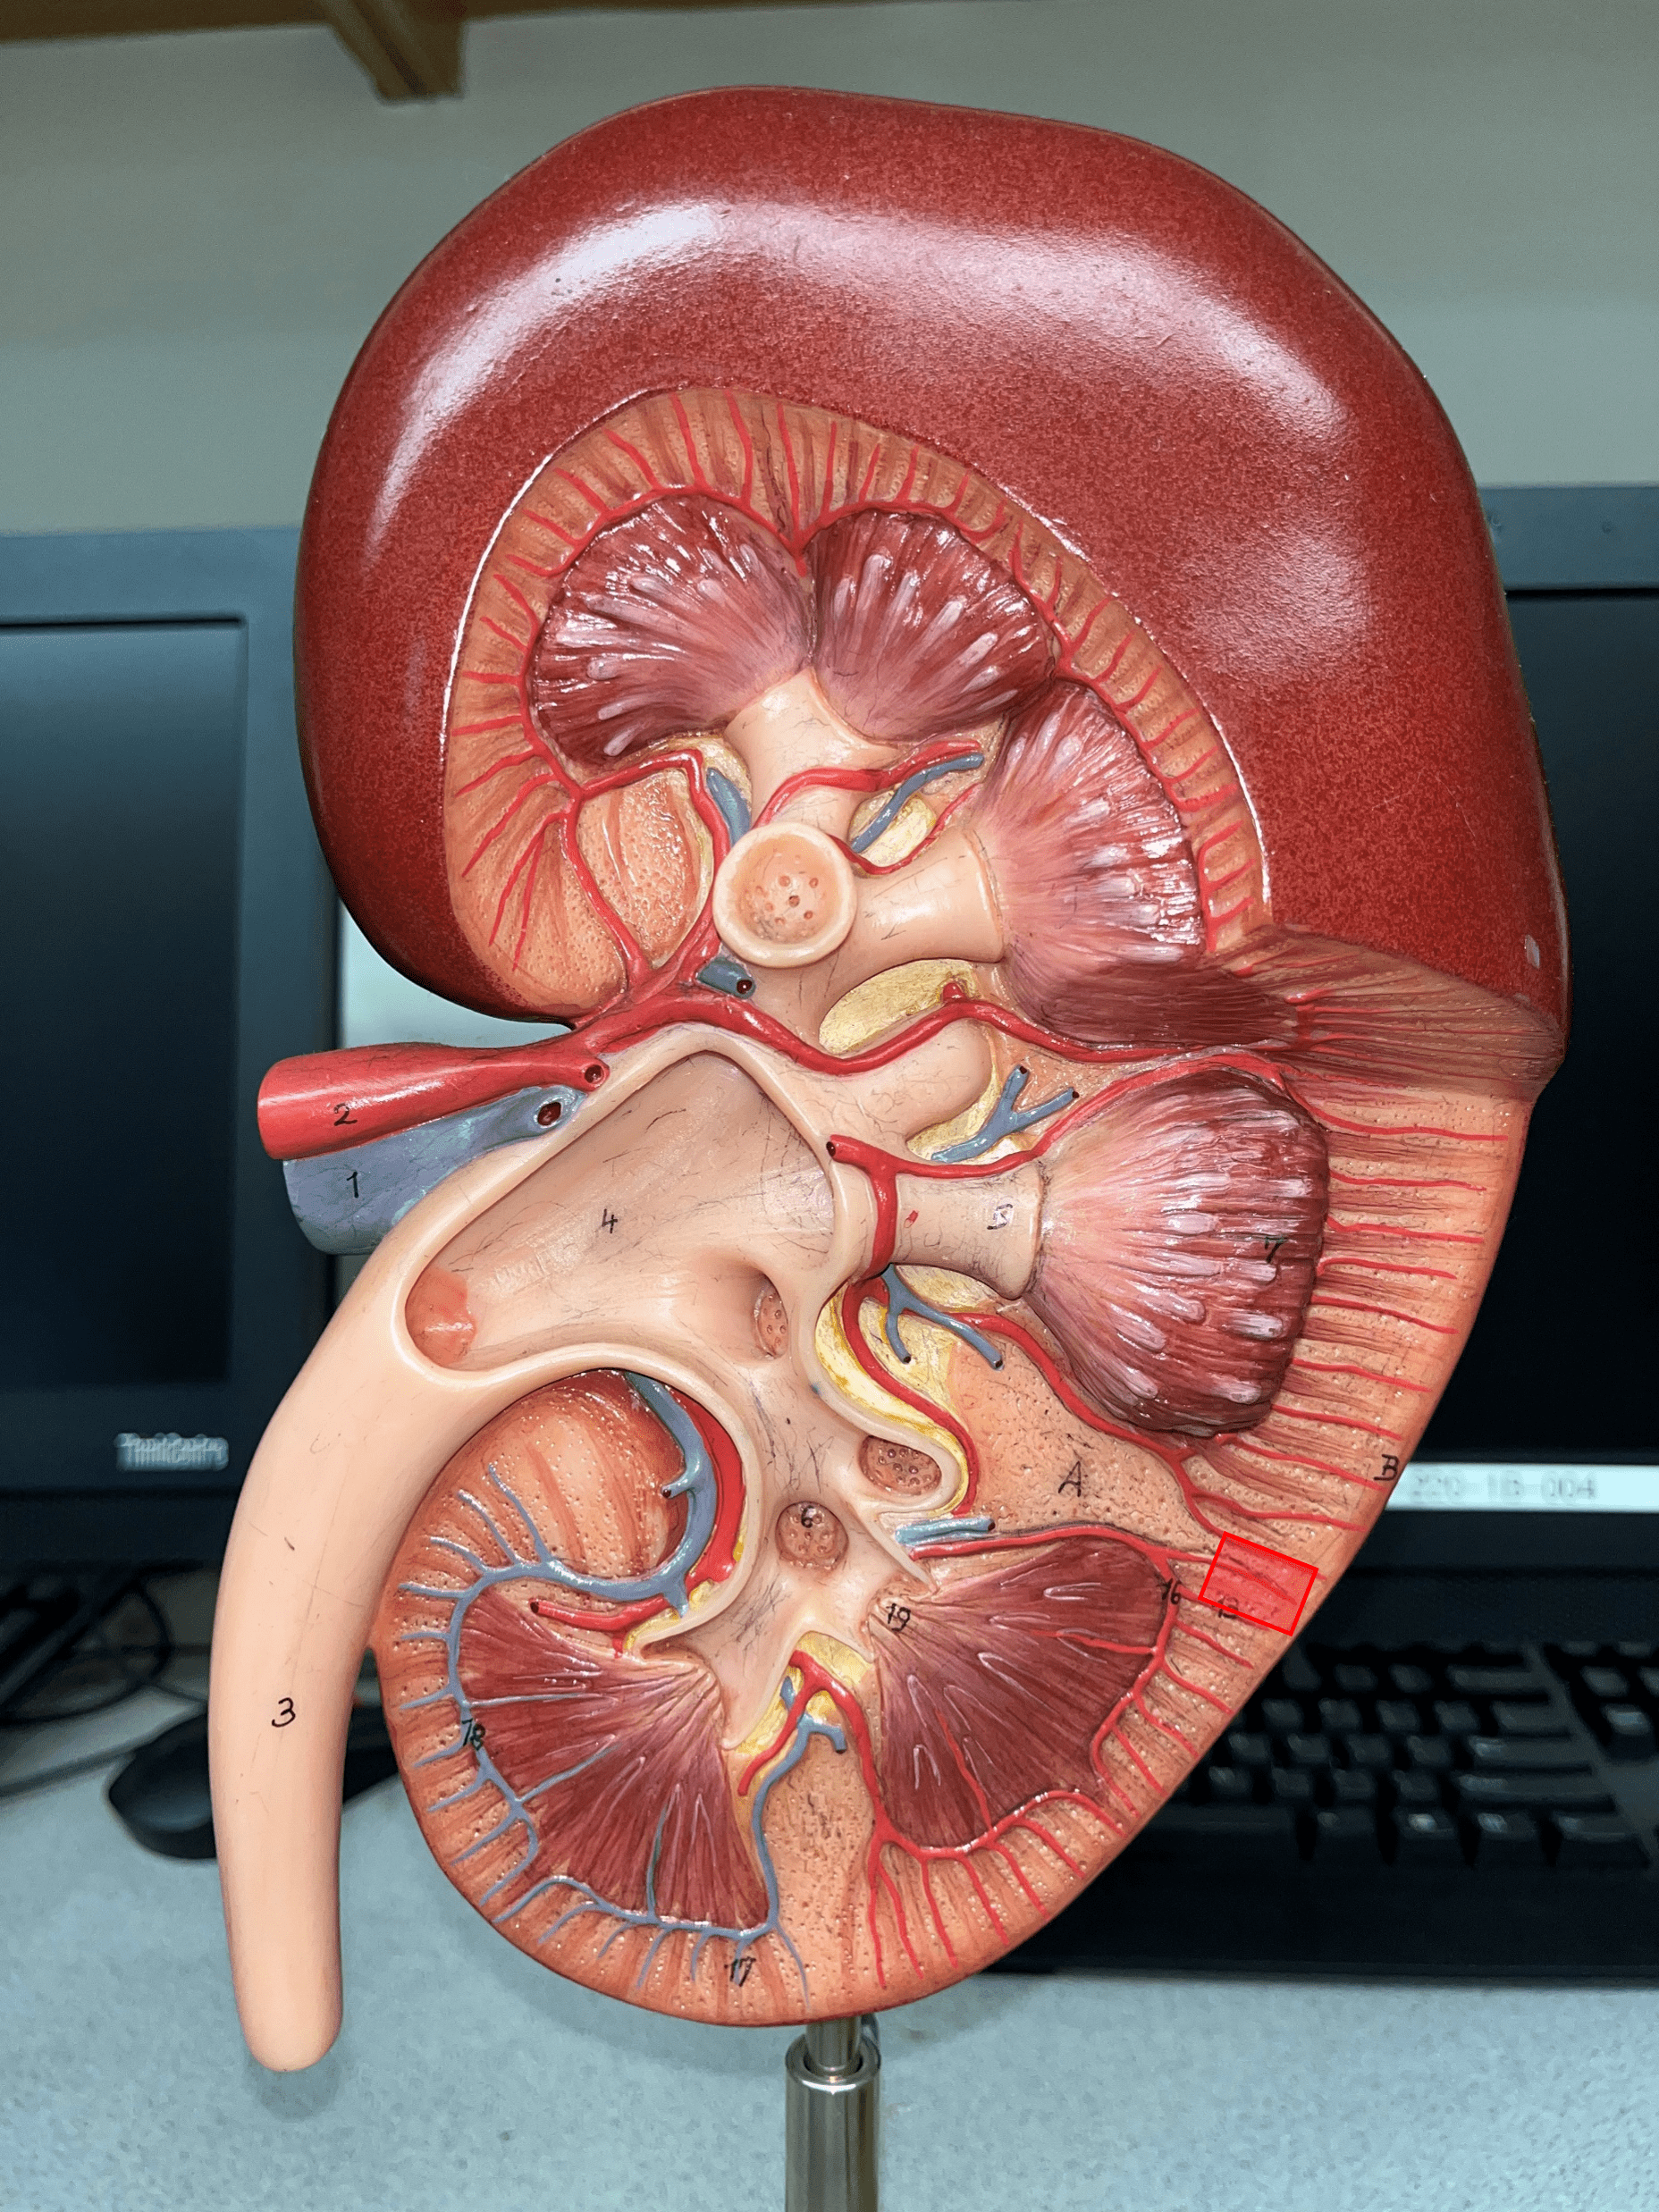

kidney

renal capsule

renal hilum

renal cortex

renal medulla

renal pyramid

renal papilla

renal column

minor calyx

major calyx

renal pelvis

renal artery

segmental artery

interlobar artery

arcuate artery

interlobular artery

interlobular vein

arcuate vein

interlobar vein

renal vein

ureter